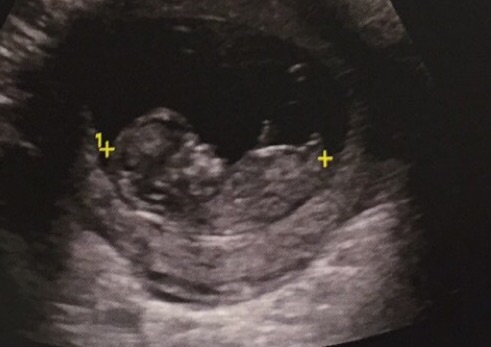

A girl. Our U/S tech took a guess, at 16 weeks, based on nub, pointed down, that it was a girl, and she was right. Pointed down = girl, Pointed up = boy. Of course it's always a toss up, but fun to guess!

Re: Bub theory boy or girl